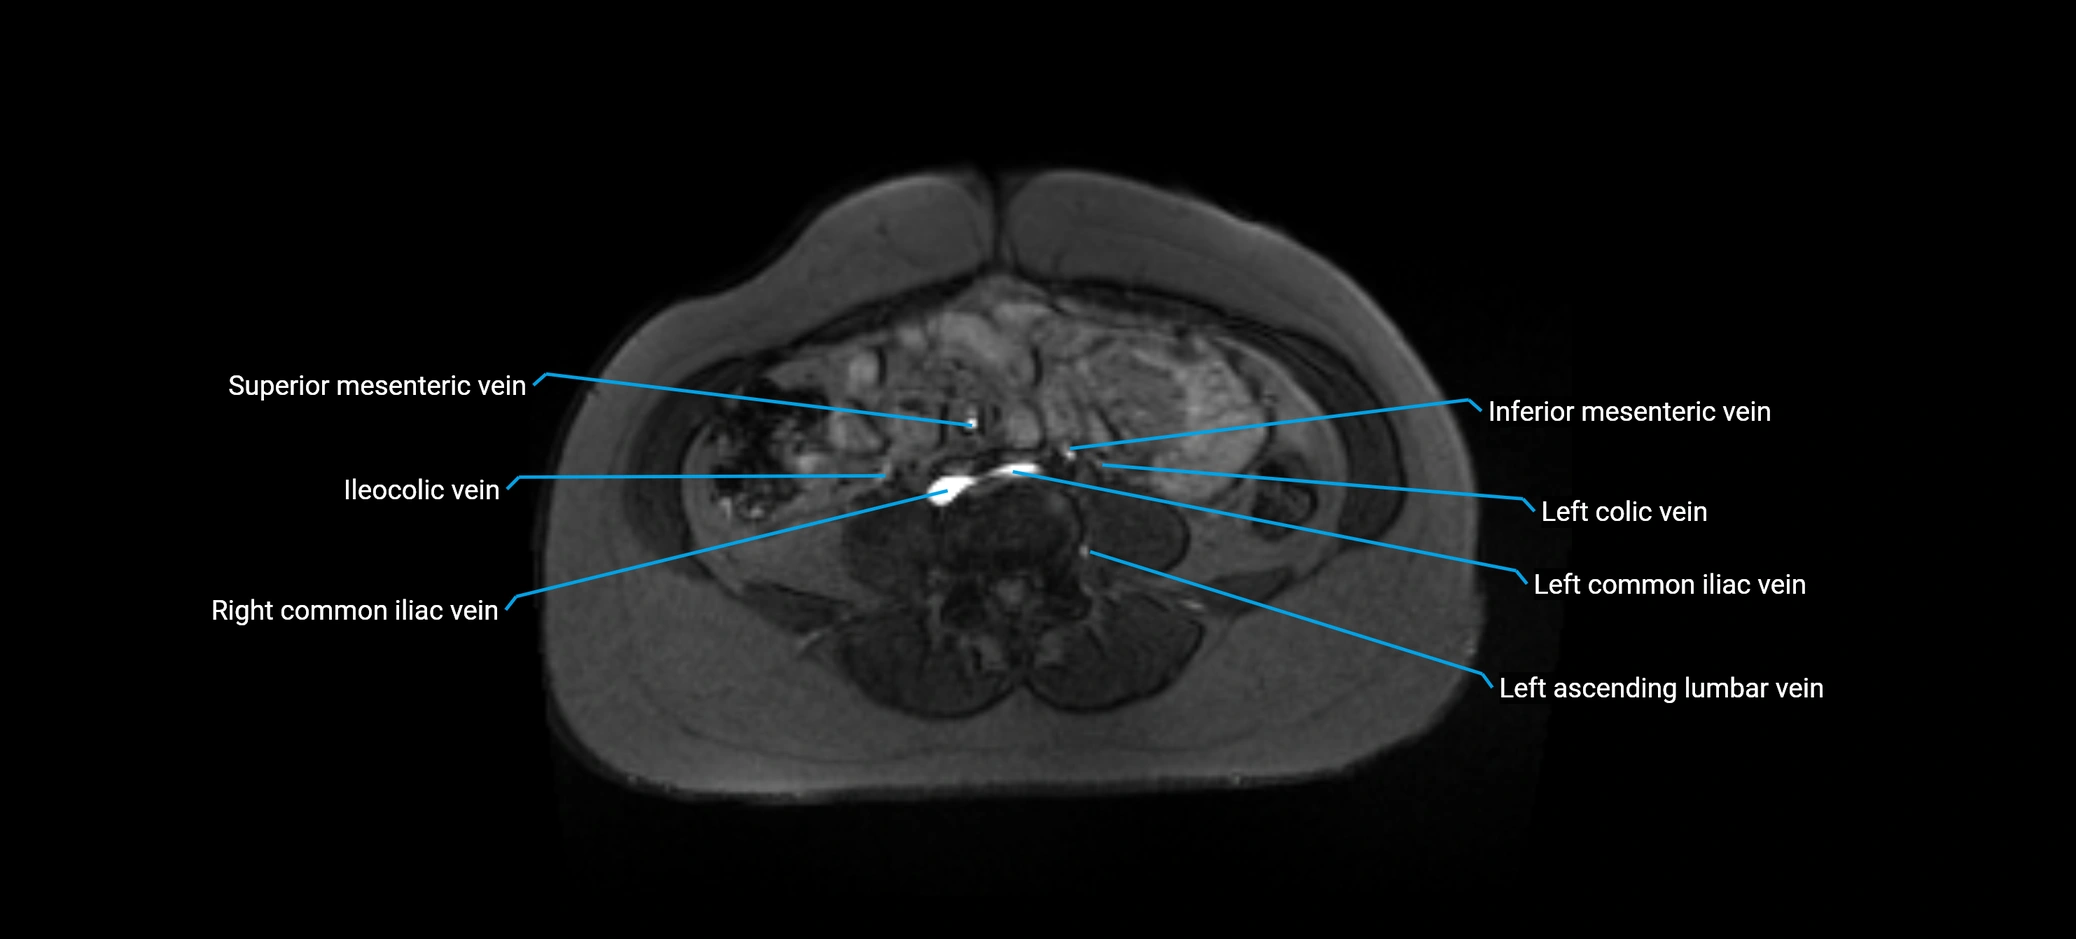

MRI image

image